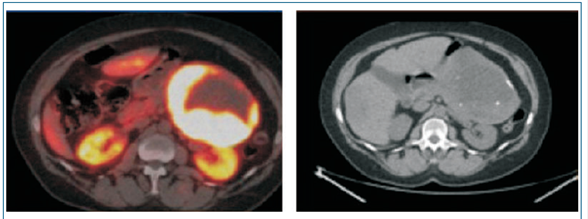

Estudio para valorar tratamiento de medicina nuclear: PET 68 Ga-DOTATATE que evidencia disminución mínima del tamaño y captación tumoral a nivel pancreático, las metástasis hepáticas no presentan cambios (figura 2).

Figura 2: PET 68Ga-DOTATATE posterior a tratamiento con lutecio 177-DOTATATE.